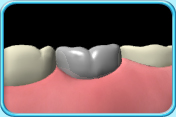

镶配不锈钢人造牙冠

银色,有固定的尺码,通常用于乳臼齿。

镶配不锈钢人造牙冠。

镶配过程